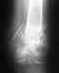

Женщина, возраст 55 лет.,вес 60кг.11.11.13 Падение с высоты 3х метров на ногу. сильная гематома на внутренней и внешней поверхности стопы. При первичном осмотре в республиканской больнице (г.Сухум) установлен диагноз: ушиб. Пациент отпущен домой.28.11.13 Сильные боли в течение двух недель.Сделан повторный рентген. Гематома спала, но полностью не рассосалась, боли уменьшились. Вторичный осмотр в военном госпитале (г.Агудзера).Диагноз: Осколочный перелом пятки со смещением.Лечение: Наложен гипс.Снимки прилагаю. Прошу помощь, по возможности, определить точность диагноза и лечения. Спасибо.

Снимок №1

Кликните для загрузки файла 3.jpg

Снимок №2

Кликните для загрузки файла 2.jpg

Снимок №3

Кликните для загрузки файла 1.jpg

Перелом пятки. Если есть возможность сделать малоинвазивный остоетсоинтез - то сделать, если нет - можно и консервативное, результат должен быть удовлетворительный.